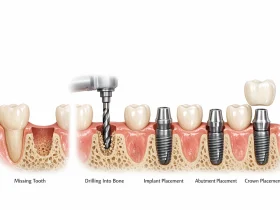

ایمپلنت دندان چیست و چگونه انجام میشود؟

ایمپلنت دندان یک جایگزین مصنوعی برای ریشه و تاج دندان است که معمولاً از جنس تیتانیوم یا مواد سازگار با بدن ساخته میشود. این پایه در استخوان فک قرار میگیرد و پس از جوش خوردن با استخوان، تاج دندانی روی آن نصب میشود. این روش مزایایی همچون حفظ ساختار استخوان، بهبود توانایی جویدن و زیبایی لبخند را فراهم میکند.